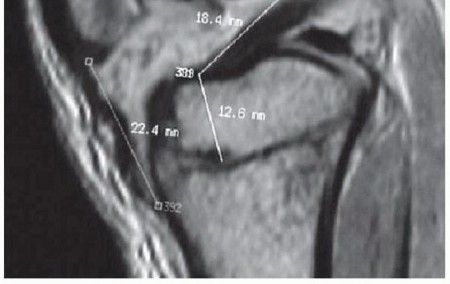

Most of the longitudinal growth of the lower extremities comes from the distal femur and the proximal tibia. The tibial physis can be as close as 15 to 20 mm to the tibial spine. The femoral physis comes within millimeters of the femoral attachment of the ACL at the most posterior aspect of its insertion (

FIG 1

).

FIG 1 • Sagittal MRI demonstrating the relationship of the ACL to the distal femoral and proximal tibial physes. (From Kocher MS, Garg S, Micheli LJ. Physeal sparing reconstruction of the anterior cruciate

*

ligament in skeletally immature prepubescent children and adolescents. Surgical technique. J Bone Joint Surg Am 2006;88[suppl, 1 pt 2]:283-293.)